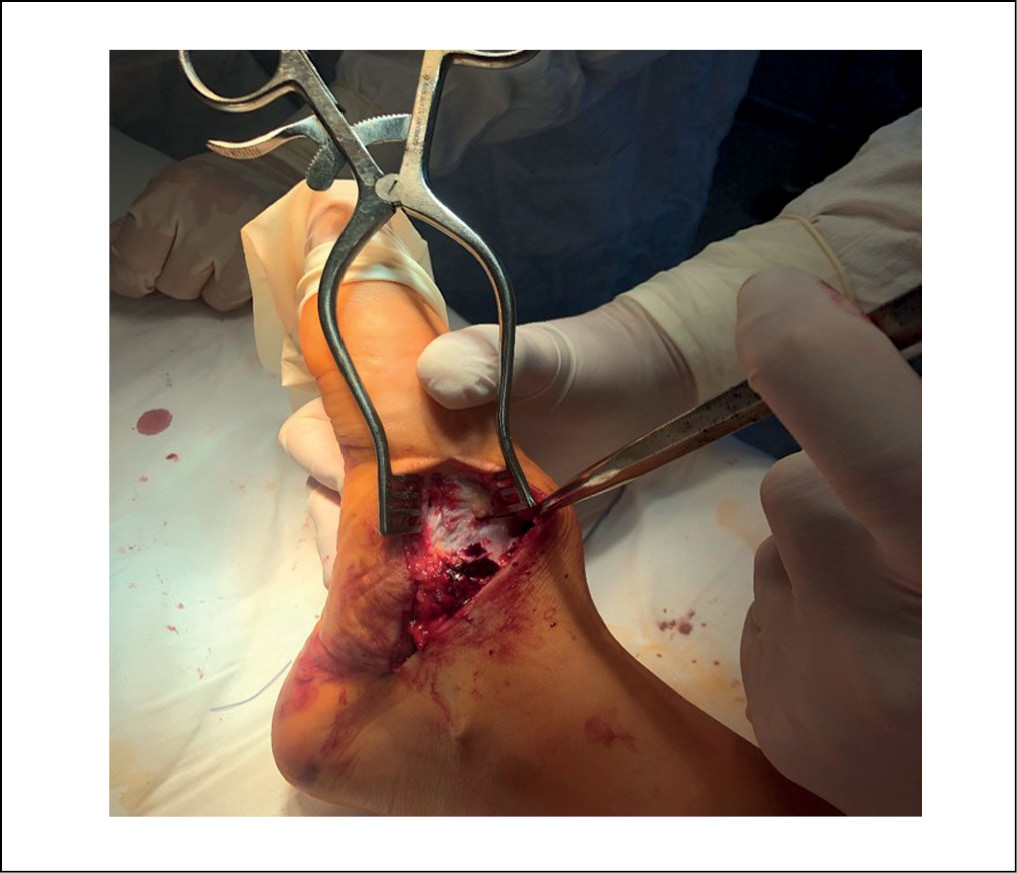

Выполняли операцию следующим образом: положение пациента лежа на спине; на среднюю треть бедра был наложен пневможгут. Производили обработку операционного поля и стерильную укладку. Первым этапом осуществляли частичную ахиллотомию по Байеру с последующей мануальной редрессацией голеностопного сустава. Далее производили сухожильно-мышечную пластику в виде транспозиции и тенодеза сухожилия передней большеберцовой мышцы в расщеп ладьевидной кости с трансоссальной фиксацией нерассасывающимся шовным материалом. Благодаря этому «формировали» поперечный свод, производя коррекцию деформации среднего отдела стопы (рисунок 3).

Рисунок 3. Формирование свода стопы. / Figure 3. Arch of the foot formation.